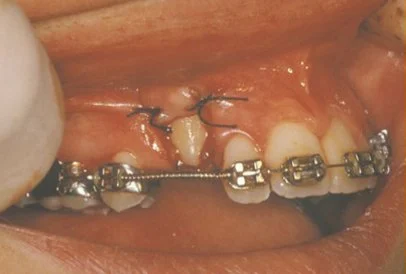

In cases where the eyeteeth will not erupt spontaneously, the orthodontist and oral surgeon will work together to get these teeth to erupt. Each case must be evaluated on an individual basis, but treatment will usually involve a combined effort between the orthodontist and the oral surgeon. The oral surgeon will expose and bracket the impacted eyetooth.

The goal is to erupt the impacted tooth and not to extract it. Once the tooth has moved into its final position, the gum around it will be evaluated. In some circumstances, there may be some minor “gum surgery” required.

Exposure and Bracketing of an Impacted Cuspid

The surgery to expose and bracket an impacted tooth is a very straightforward surgical procedure that is performed in the oral surgeon’s office. For most patients, it is performed using laughing gas and local anesthesia. In selected cases it will be performed under IV sedation if the patient desires to be asleep, but this is generally not necessary for this procedure. If the procedure only requires exposing the tooth with no bracketing, the time required will be shortened by about one half. These issues will be discussed in detail at your preoperative consultation with your doctor.